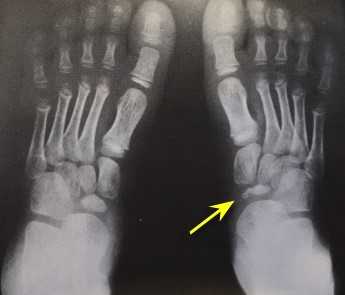

При клиническом осмотре определяется умеренный отёк в средней части переднего отдела стопы, при пальпации боль в проекции 2 плюсне-фалангового сустава. При оценке амплитуды движений во втором плюсне-фаланговом суставе провоцируется боль, движения качательные, амплитуда менее 5 градусов. На рентгенограммах отчётливо видны разрастания костной ткани в области головки 2 плюсневой кости и свободное внутрисуставное тело.